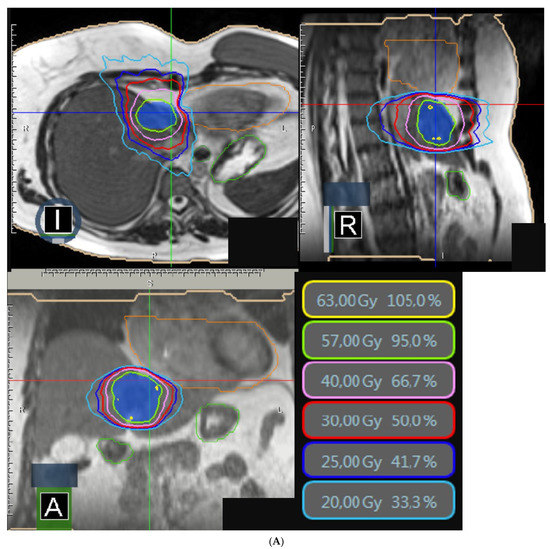

Stereotactic MR-Guided Radiotherapy for Liver Metastases: First Results of the Montpellier Prospective Registry Study

by Karl Bordeau, Morgan Michalet, Aïcha Keskes, Simon Valdenaire, Pierre Debuire, Marie Cantaloube, Morgane Cabaillé, William Jacot, Roxana Draghici, Sylvain Demontoy, Xavier Quantin, Marc Ychou, Eric Assenat, Thibault Mazard, Ludovic Gauthier, Marie Dupuy, Boris Guiu, Céline Bourgier, Norbert Aillères, Pascal Fenoglietto, David Azria and Olivier Riouadd Show full author list remove Hide full author list

J. Clin. Med. 2023, 12(3), 1183; https://doi.org/10.3390/jcm12031183 - 2 Feb 2023

Liver stereotactic body radiotherapy (SBRT) is a local treatment that provides good local control and low toxicity. We present the first clinical results from our prospective registry of stereotactic MR-guided radiotherapy (MRgRT) for liver metastases. All patients treated for liver metastases were included [...] Read more.

Liver stereotactic body radiotherapy (SBRT) is a local treatment that provides good local control and low toxicity. We present the first clinical results from our prospective registry of stereotactic MR-guided radiotherapy (MRgRT) for liver metastases. All patients treated for liver metastases were included in this prospective registry study. Stereotactic MRgRT indication was confirmed by multidisciplinary specialized tumor boards. The primary endpoints were acute and late toxicities. The secondary endpoints were survival outcomes (local control, overall survival (OS), disease-free survival, intrahepatic relapse-free survival). Twenty-six consecutive patients were treated for thirty-one liver metastases between October 2019 and April 2022. The median prescribed dose was 50 Gy (40–60) in 5 fractions. No severe acute MRgRT-related toxicity was noted. Acute and late gastrointestinal and liver toxicities were low and mostly unrelated to MRgRT. Only 5 lesions (16.1%) required daily adaptation because of the proximity of organs at risk (OAR). With a median follow-up time of 17.3 months since MRgRT completion, the median OS, 1-year OS and 2-year OS rates were 21.7 months, 83.1% (95% CI: 55.3–94.4%) and 41.6% (95% CI: 13.5–68.1%), respectively, from MRgRT completion. The local control at 6 months, 1 year and 2 years was 90.9% (95% CI: 68.3–97.7%). To our knowledge, we report the largest series of stereotactic MRgRT for liver metastases. The treatment was well-tolerated and achieved a high LC rate. Distant relapse remains a challenge in this population. Full article